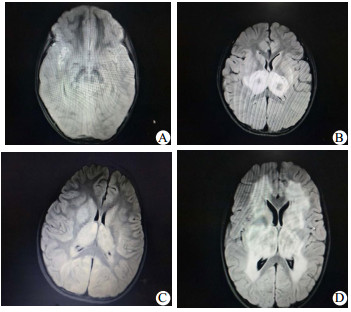

10例患儿入院前或入院时均积极完善头颅CT,头颅CT可见丘脑、基底节、脑干对称性低信号影(表 2)。4例患儿在入院后2~5 d完善头颅MRI,4例患儿头颅MRI提示病灶呈长T1长T2信号,FLAIR可见同心圆环状混杂信号(图 1)。通过完善呼吸道合胞病毒、肠道病毒、禽流感病毒核酸检测、支原体、衣原体、痰培养、血培养、脑脊液培养、尿培养病原学分析发现6例流感A阳性,5例核酸检测提示H1N1,1例核酸检测提示H1N3,1例流感B阳性,1例肠道病毒通用型阳性,2例相关病原学检测均阴性(表 1)。

| A:病例1,患儿入院第3天诊断脑死亡,家属要求继续要求治疗,住院89天后家属自行联系康复科医院康复治疗;B:病例2,住院12天出院,没有遗留神经系统异常表现,出院时ADL评分Ⅰ级;C:病例5住院第3天拔出气管插管,住院15天出院,出院时神志转清,但不会讲话,有傻笑,需鼻饲喂养,康复中,ADL评分Ⅳ级;D:病例8,患儿住院第5天拔出气管插管,住院15天出院,出院仍处于昏迷中,昏迷评分7分,康复中,ADL评分Ⅳ级 图 1 四例患儿头颅磁共振结果 |

本组的10例患儿临床症状表现为感染后发热的1~3 d内出现神经功能迅速恶化,精神状态改变,迅速出现癫痫发作,从而进入昏迷状态,7例院外气管插管入科,2例入院后即刻需要呼吸机辅助呼吸。生化资料提示均存在不同程度的谷丙转氨酶、谷草转氨酶、肌酸激酶同工酶的升高。头颅影像学揭示了双侧丘脑的多灶性病变,此外,脑干、脑室、脑室周围白质和其他区域的变化可以存在。本组10例患儿均完善头颅CT,头颅CT都发现不同程度丘脑、基底节、脑干、小脑对称性低信号影;4例患儿完善头颅MRI,病灶呈长T1长T2信号,FLAIR可见同心圆环状混杂信号(图 1)。目前国内仅有个例报告,王华等[11]总结4例急性坏死性脑病,头颅MRI发现除了双侧丘脑对称性长T1、长T2信号外,大脑、小脑及脑干也有受累。